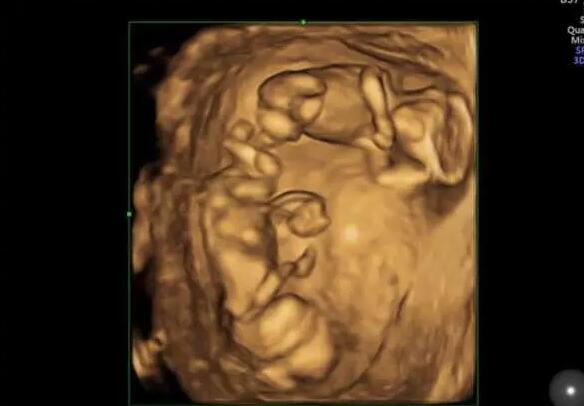

022临沂市人民医院做试管婴儿取卵只有2个能成功吗?

试管婴儿的成功率并不取决于卵泡的数量,而是取决于卵泡的质量。因此,卵泡数量少不要太担心,临沂市人民医院做试管婴儿的成功率是相对较高的,临沂市人民医院做试管婴儿的成功率具体如下:

1.临沂市人民医院生殖科每年有近10万名不孕不育症患者接受治疗,完成新鲜、解冻周期超过10000个,总成功率约为53%-55%。在该医院做试管婴儿取卵只有两个卵子,如果两个卵泡的质量较好,即使只有两个卵泡,成功率也相对较高,可以达到50%左右;

2.但是如果卵泡质量不好,成功率会稍微低一些,可能只有30%-40%;

以上就是“2022临沂市人民医院试管婴儿成功率一览,取卵只有2个能成功吗?”的全部内容了,事实上,做试管婴儿并不是卵泡越多越好,即使卵泡的数量再多,质量不好,也是徒劳的。